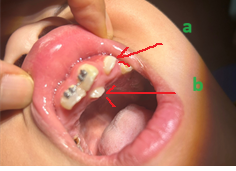

Răng thừa (b) mọc trong vòm miệng khiến cho R22 (a) mọc lệch xoay trục XQ răng toàn cảnh không thấy răng thừa do R21 (a) che khuất,(b) là R22 bị xoay trục

Hình ảnh răng thừa (a) xuất hiện rất rõ trên CT Cone Beam, (b) là hình ảnh R21

Hình 3: Tính ưu việt của CT Cone Beam trong chẩn đoán răng thừa

(Nguồn: Bệnh viện Đa khoa Tỉnh Quảng Trị)